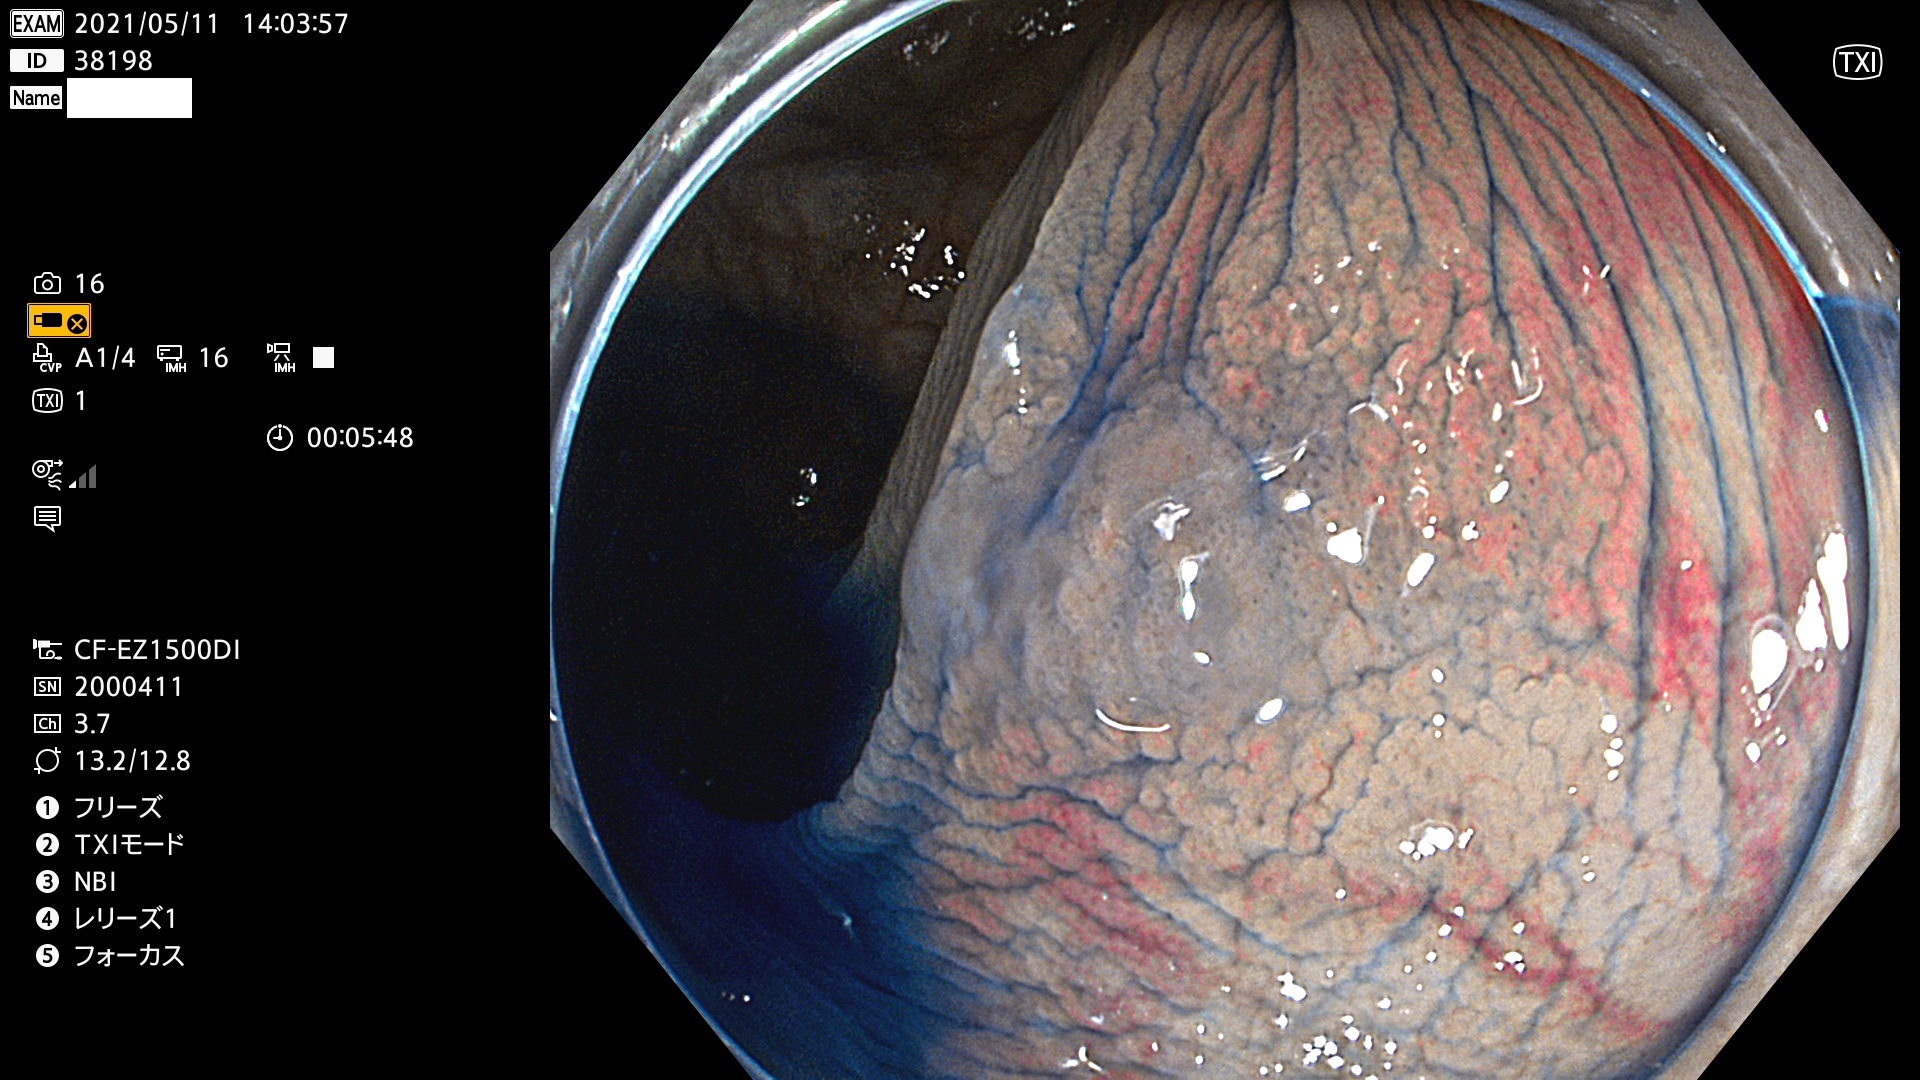

腺腫発見率 72 % (カルテ番号 38100〜38199の100名の方の検査結果で集計)大腸癌検診最新情報

以下のカルテ番号の方に腺腫(Adenoma,Group3〜5)が見つかりました(集計法)

38101 38103 38104 38106 38107 38108 38109 38110 38111 38112 38113 38114 38115 38117 38118 38122 38123 38124 38125 38126 38127 38128 38130 38131 38132 38135 38137 38138 38140 38141 38142(SSAPのみ) 38143 38144 38145 38146 38147 38148 38149 38150 38151 38152 38153 38154 38157 38158 38160 38161 38162 38164 38165 38166 38167 38168 38169 38172 38176 38177 38178 38181 38182 38183 38184 38187 38189 38190 38191 38192 38193 38194 38195 38196(SSAPのみ) 38198

発見困難で危険性の高い平坦型病変(上記100名より抽出) ![]()